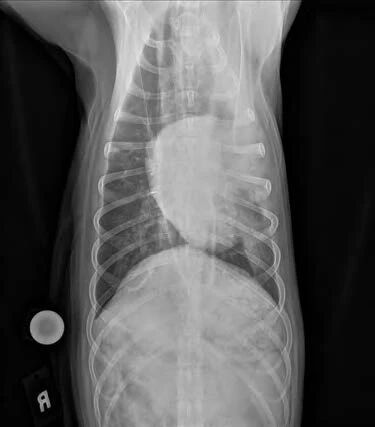

- 胸部X光片:食管弥漫性扩张。

- 食管可以充满空气、液体或食物。

–如果存在吸入性肺炎,可见肺浸润(图1-2)。

图2. 腹背侧胸部X光显示食管扩张和吸入性肺炎。